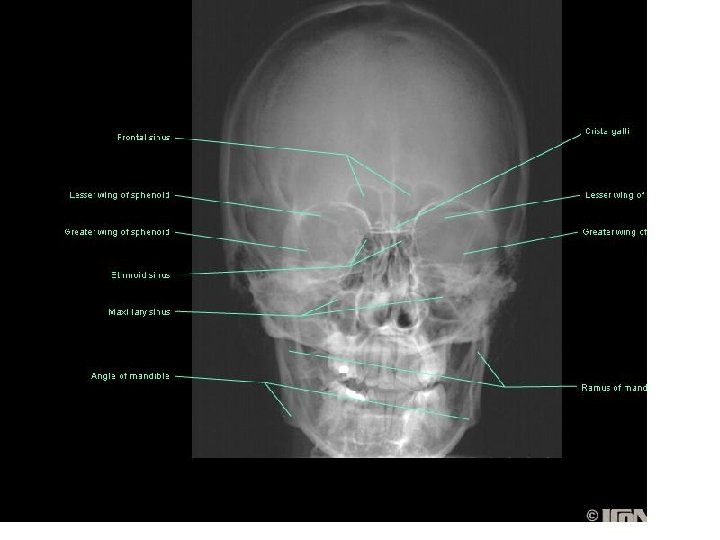

Nasal cavity Nostriles (nares) Choana Roof: body of the sphenoid, cribriform plate of the

Nasal cavity Nostriles (nares) Choana Roof: body of the sphenoid, cribriform plate of the ethmoid, frontal bone, nasal bones, nasal cartilages Floor: maxilla, palatine Medial wall: nasal septum Lateral walls: contain sup. , middle & inf. Nasal conchae.

Paranasal Sinuses

Frontal sinus

Ethmoidal sinusitis